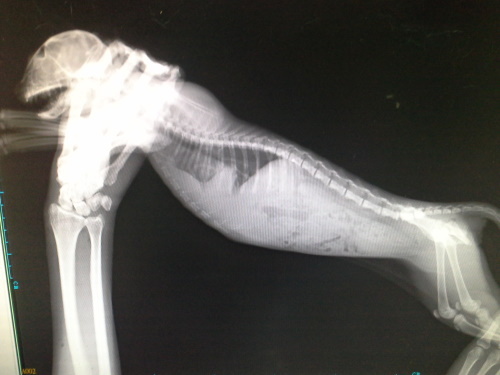

主題: 貓咪求助醫療協助 申請者姓名: 郭崑杉 花色: 申請日期: 2014-08-05 14:36:35 申請者部落格: 申請者臉書網址: 所在縣市/合作醫院: 新竹市/新竺動物醫院 治療費用: 17950元 需求人數: 20人 已結案 (2014-11-12 11:48:35) 報名人員: Patrick x2(已付款)、Wendy Kao(已付款)、JuJu x4、JuJu x2、JuJu x3、JuJu x3(已付款)、Ivy Hsu(已付款)、lavinia x2(已付款)、Ed Tsai x2(已付款)、peiyu(已付款)、Bella Hung(已付款)、chiawei(已付款)、薛、薛(已付款)、Bow Huang x2(已付款)、Fionna Hsu x2(已付款)、胡衿綾(已付款)、 候補人員: 動物病情說明: 這隻白灰貓咪呼吸非常急促,本來以為是鼻氣管炎,7/17送醫治療,貓咪偏瘦,喘,鼠蹊處瘀血,貓瘟檢驗陰性,Xrays顯示胸腔有異物,懷疑橫膈赫尼亞肝臟進入胸腔中,且血檢肝指數偏高,小貓精神食慾非常好,擔心但時間拖久了對貓咪不利,於7/28手術,術中發現肝臟在胸腔中,已有黏連狀況發生,雖然手術順利完成,但因為胸腔的壓力改變,身體無法負荷於術後死亡。